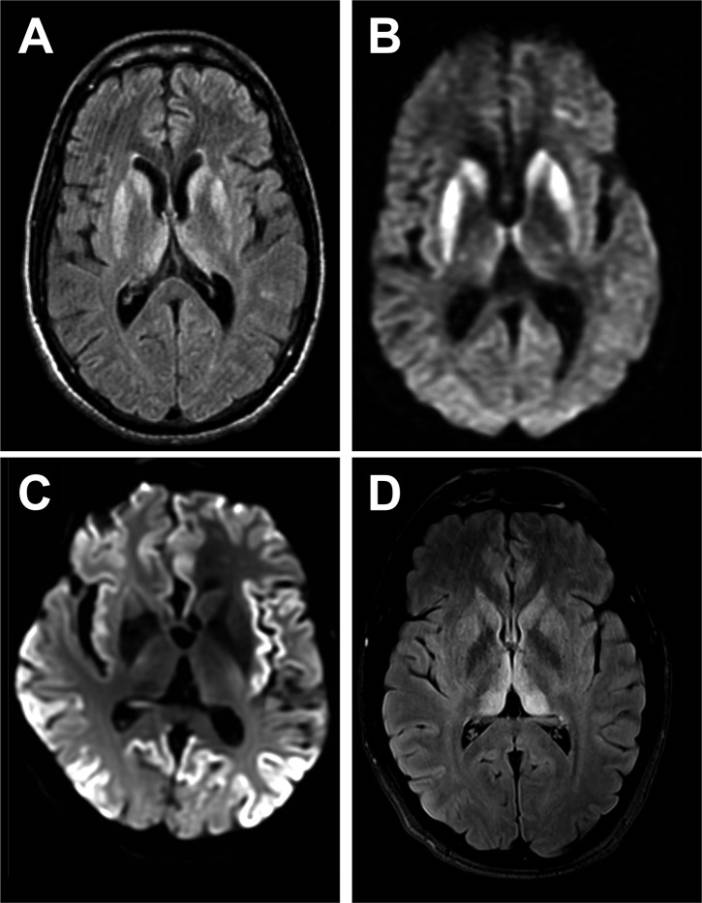

Tanı yöntemleri geliştirilmeli, erken teşhis için biyobelirteçler, görüntüleme yöntemleri üzerine odaklanılmalı.